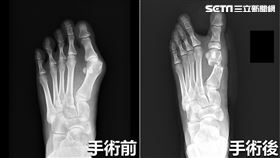

不忌口下場慘!痛風石比雞蛋大破裂還爆漿

62歲黃男長年患有痛風卻仍不禁口,日前左腳踝突然劇烈...

2026/03/18 09:00